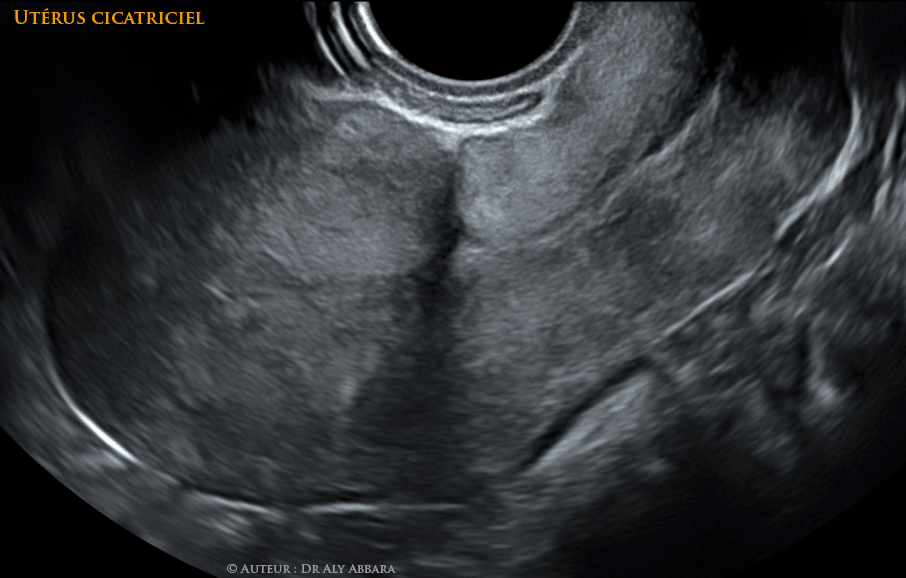

• Séquence vidéo et image animée montrant l'aspect habituel de la cicatrice de l'hystérotomie segmentaire transversale réalisée lors des césariennes : cicatrice linéaire antéro-postérieure (sur la coupe sagittale de l'utérus) ne comportant pas de niche liée à la désunion partielle ou totale des berges de la cicatrice.

• A comparer à l'aspect de cette cicatrice quand elle est compliquée d'une isthmocèle c’est-à-dire d'une déhiscence secondaire à un défaut de cicatrisation.